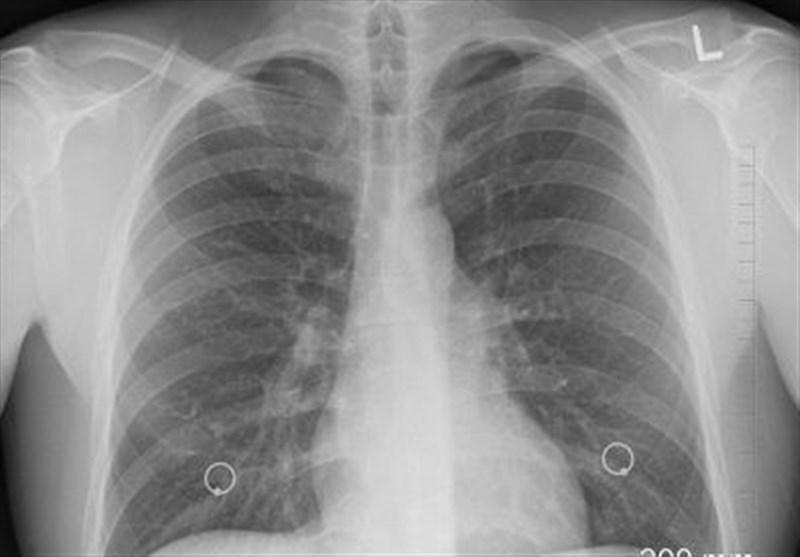

وی عنوان کرد: سرطان ریه یکی از پنج سرطان کشنده در جهان است. به دلیل تهاجمی بودن، زمان کمی برای درمان باقی میگذارد و متاسفانه بسیاری از بیماران در سالهای اول فوت میکنند. میزان ابتلا در بخش مردان حدود 12.7 در هر صد هزار نفر و در میان زنان رقمی کمتر از مردان است. در استان گلستان اما میزان شیوع این بیماری بالاتر است و در مردان میزان ابتلا 21.3 در هر صد هزار نفر (بسیار بالاتر از میانگین کشوری) و در میان زنان 5.21 در هر صد هزار نفر است.

روشندل با اشاره به عوامل خطر شناخته شده سرطان ریه گفت: مصرف سیگار (ریسک بسیار بالا)، در معرض دود سیگار بودن، مصرف الکل و نوشیدنیهای الکلی، مواجهه شغلی با تشعشعات (مثل برخی محیطهای بیمارستانی یا صنعتی)، آلودگی هوا و آب، تریاک (به عنوان یک عامل خطر مهم و خاص در کشور) است.